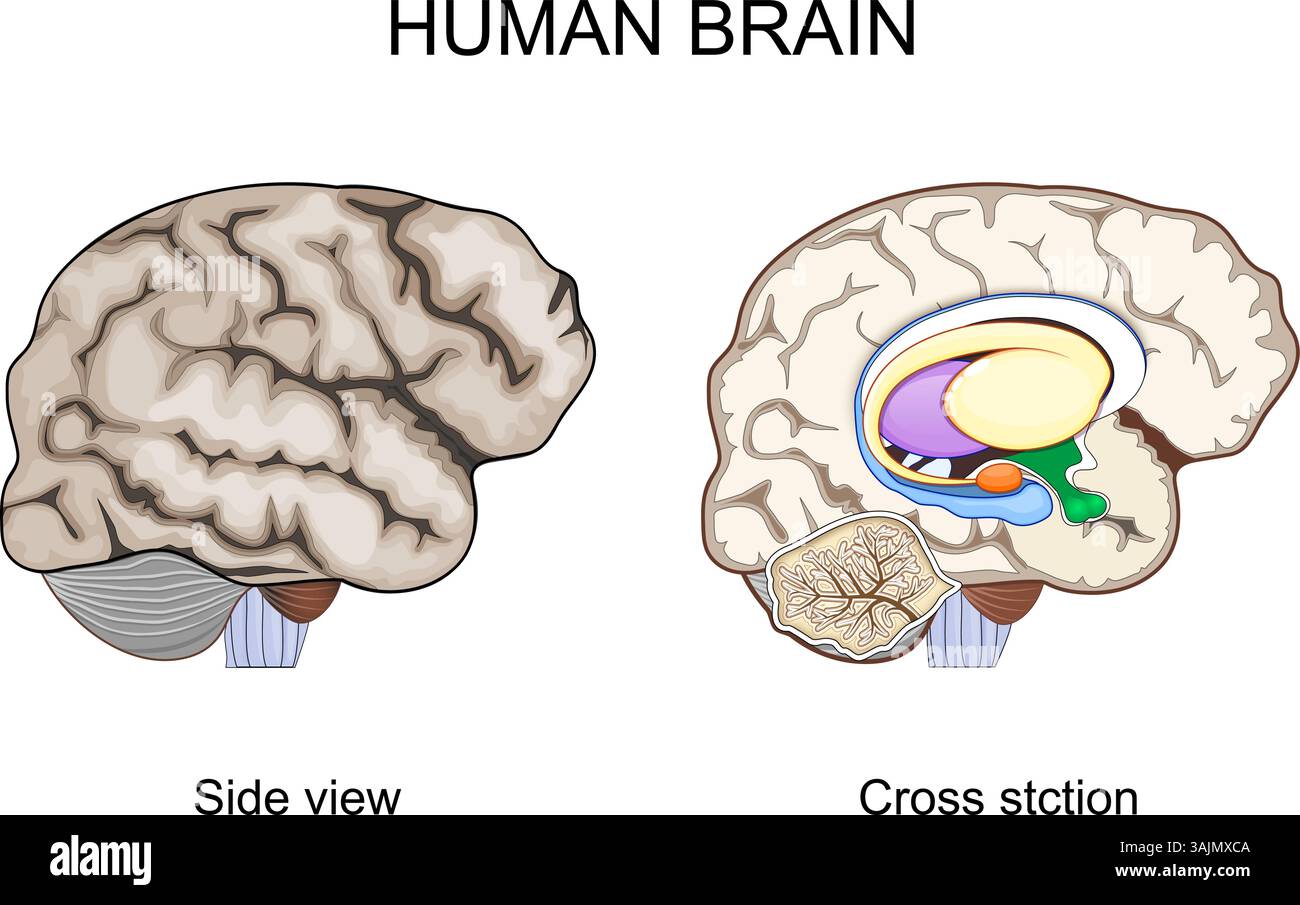

RF3AJMXCA–Anatomia cerebrale. Vista in sezione trasversale. Vista laterale della corteccia cerebrale. Sistema nervoso centrale. Neuroanatomia. Strutture cerebrali umane. Diagramma schematico.